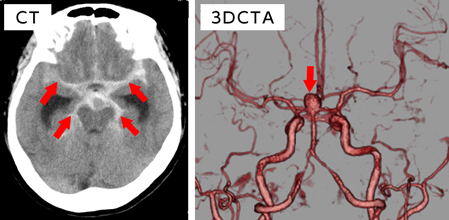

60代女性、脳動脈瘤破裂によるくも膜下出血

意識障害にて発症し、救急車にて来院。

写真左:頭部CTにてくも膜下出血を認める(矢印)。

写真右:3DCTAngiographyにて脳底動脈に長径10mmの動脈瘤を認める(矢印)。